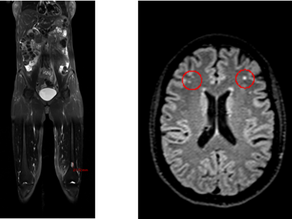

Beyond Repair: The Link Between the FRAT Test, Autism, Gut Biome, Inflammation, Toxin Burdens, and Leucovorin

Introduction Autism Spectrum Disorder (ASD) is a complex neurodevelopmental condition influenced by genetic, environmental, and...